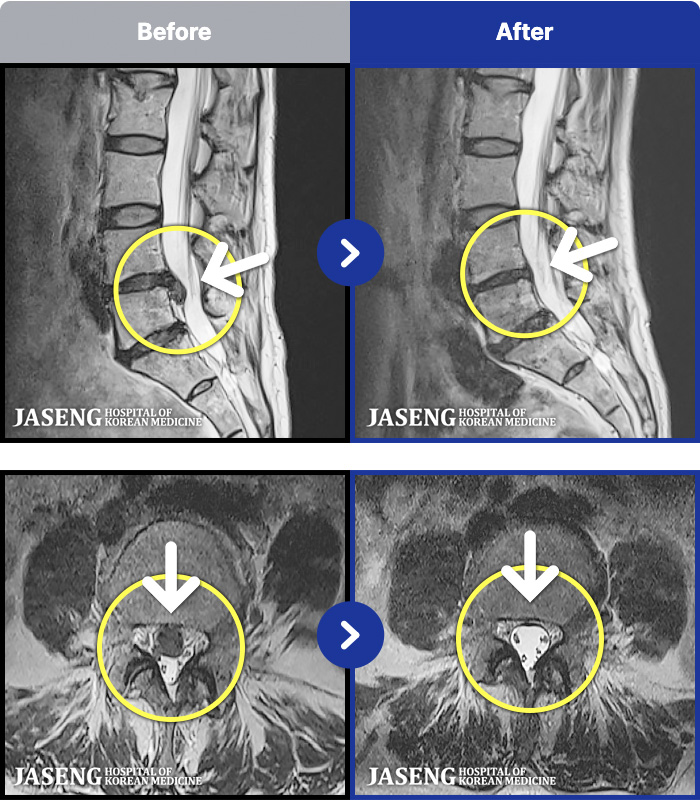

MRI ġ

MRI ũ ʸ Ȯϼ.